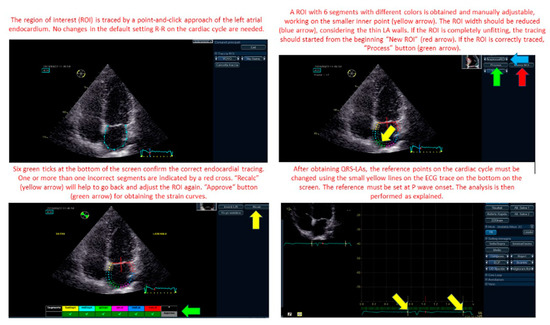

2.3. Speckle Tracking Echocardiography